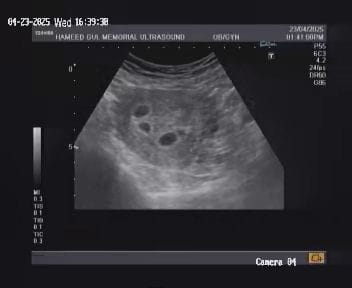

Ultrasound images

Our institutue provides high-quality ultrasound imagies for various diagnostic applications. these images serve as essential tools for accurate diagnostic and treatment planning.